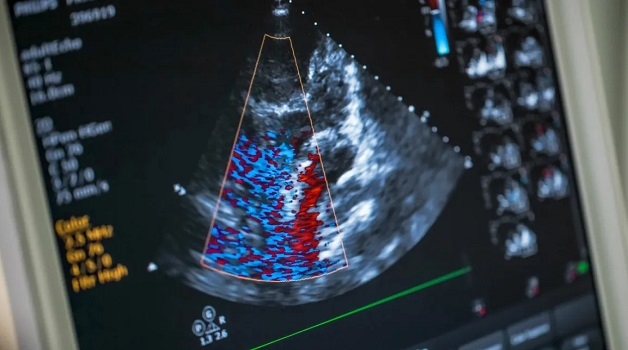

Hình ảnh siêu âm tim hiển thị trên màn hình.

– Siêu âm Doppler: Hỗ trợ quan sát điện tâm đồ và nhận biết dòng máu ở thì tâm thu, tâm trương hay ở cả hai thì. Siêu âm Doppler có nhiều dạng như Doppler liên tục, Doppler xung, Doppler tổ chức hoặc Doppler màu.